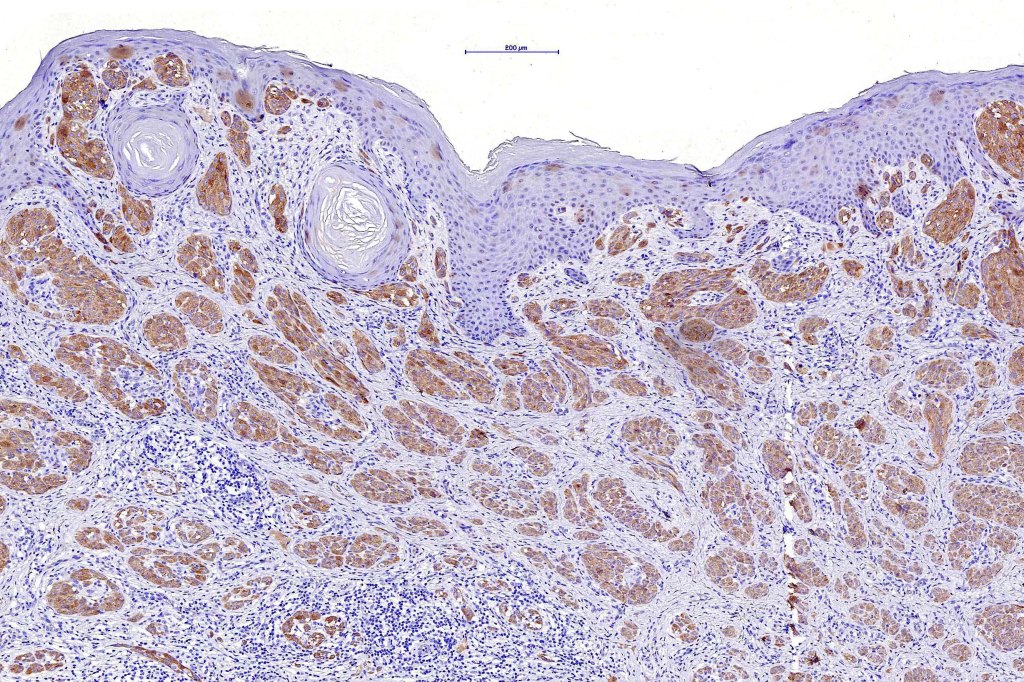

•Matures with depth-often best recognized at scanning/low power magnification & readily confirmed with S100 or MART1

•Maturation implies nest size and cell size diminishing with depth, at the base, the infiltrate may have a single cell infiltrating pattern

•Spitz nevus has been shown to be associated with receptor tyrosine kinase mutations including ALK, ROS, RET, & NTRK1-3, MET, mutations in HRAS or MAP2Ki, copy number gains of 11p

•S100, MART1 & SOX10 +ve, HMB45 +ve (superficially & lost progressively with depth), p16 +ve, p21 +ve